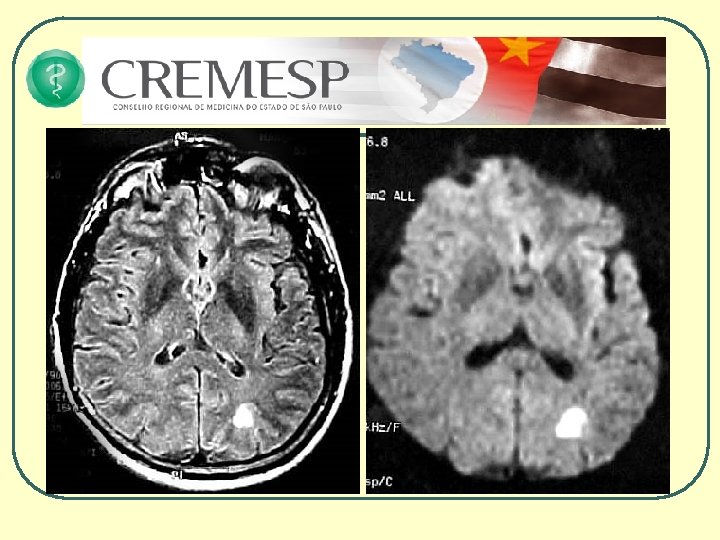

Vantagens da RM • Capacidade multiplanar • Melhor caracterização da lesão tecidual • Quanto ao tipo • Quanto à gravidade • Quanto à localização • Quanto à extensão • Melhor visualização do tronco cerebral • Angiografia • Difusão e Perfusão • Espectroscopia Programa de Educação Médica Continuada do CREMESP

AVCI há 3 horas

AVCI há 48 horas